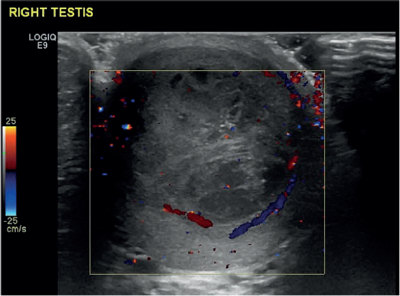

A 26-year-old male presented with a two-week history of testicular pain and swelling. On examination the right testicle was enlarged, indurated and tender. Erythema of the scrotum on that side was also noted. Ultrasound of the testis reported a distorted right testicle with irregular solid and cystic components suggestive of a focal abscess with an inflammatory mass (Figure 1). Doppler study confirmed absence of any obvious internal vascular signal but with an increase in the peripheral vasculature (Figure 2).

Figure 2.